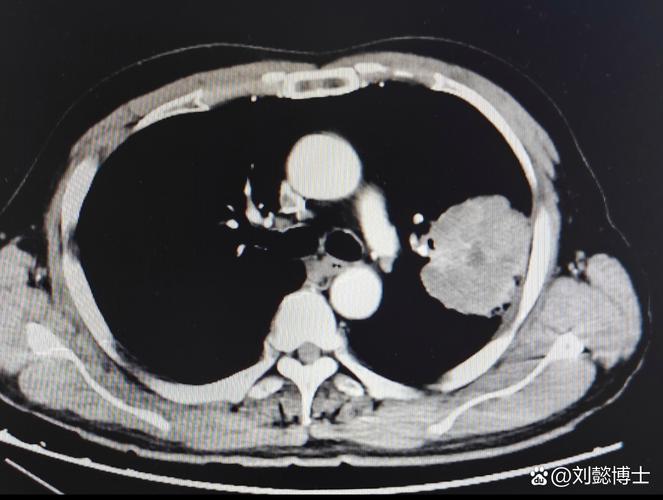

提问说著名作家经常作检查,是三年一次还是每年一次?若三年的话,那癌组织从微小形态到中晚期形态,已有足夠的发展时间。就算一年一次也难免保证检查时就发现,肺癌有小细胞癌、鳞癌、腺癌、大细胞癌等之分,其发展进程各不相同,有的缓慢有的迅猛,如不幸患上恶性程度较高的小细胞癌,一年的时间也可能达到中晚期。

回到本例,肺癌发展速度不好说,如果有做CT项目,而且前后时间区间不短,医院有正常拍片读片。那医院无责,毕竟癌症发展速度没有标准。。。